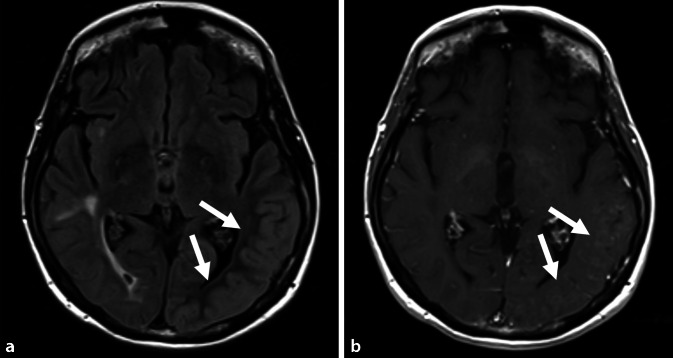

In Abb. 1 (a FLAIR axial, b kontrastangehobene T1-gewichtete Sequenz) ist jeweils der Zeitpunkt der akuten Symptomatik bestehend aus einer Gesichtsfeldeinschränkung, Wortfindungsstörungen, Orientierungsschwierigkeiten und den Kopfschmerzen erfasst. Hierbei sind deutlich eine Schwellung sowie Schrankenstörung der betroffenen Hirnareale (siehe weiße Pfeile) im Sinne einer Kontrastmittelaufnahme links temporal dargestellt. In der Diffusionswichtung ergaben sich entsprechend geringe kortikale Signalsteigerungen mit korrelierenden Signalabsenkungen in der „apparent diffusion coefficient map“ (ADC; Abb. 2). Gefäßirregularitäten zeigten sich in der CT-Angiographie und MR-TOF („time of flight“-Sequenz) nicht.